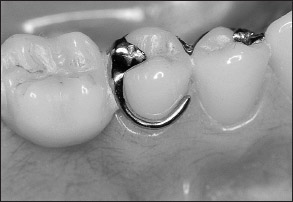

Traditionally, fixed partial dentures have been attached to abutments using dental cements, while removable partial dentures have been attached to abutments by other means. In removable partial denture prosthodontics, there are two principle types of retainers. They are termed extracoronal retainers and intracoronal retainers. Extracoronal retainers consist of two fingers of metal (ie, clasps) that lie on the surface of a clinical crown (Fig 1-3). One finger of metal is termed a retentive clasp, while the other is termed a reciprocal clasp. The retentive clasp is located in an undercut area of the clinical crown and resists displacement of the prosthesis away from the underlying hard and soft tissues. The reciprocal clasp is located in a non-undercut area and serves as a bracing or stabilizing element for the prosthesis. The resultant assembly is termed an extracoronal retainer because the retentive and reciprocal components lie on the external surfaces of an abutment.

Fig 1-3 Components of an extracoronal retainer usually include a rest, retentive and reciprocal clasps, and a proximal plate.